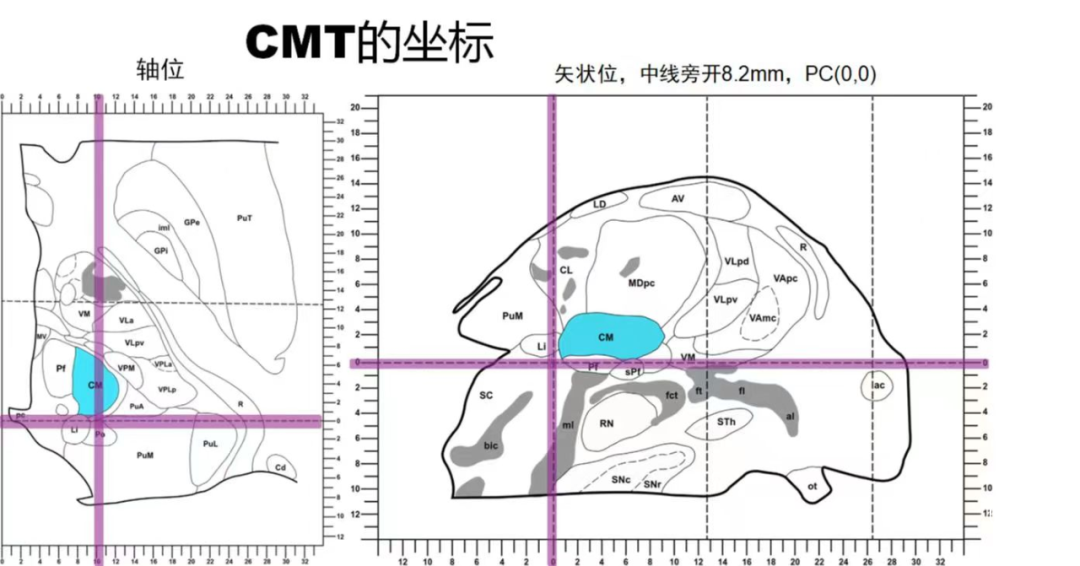

患者于5月龄首发,诱因:发热1周,热峰40℃,表现为发热第1天出现双眼上翻,无肢体抽搐,持续数分钟;15月龄学步后发现行走易跌倒,坐位时出现头颈及躯干向一侧倾斜,每次持续2-3秒,每天发作数次,声音刺激可诱发;病程中仅17岁出现1次全身僵直抖动;23岁后发作较前稍有缓解,声音刺激无发作,平均1-3次/天,表现为:发作性肢体僵直,每次持续2-3秒;患者幼年起病,辗转多家医院仍发作频繁,反复跌倒至头面部频繁外伤。后转求我院,完善脑电图检查提示清醒期背景活动正常(图1),间歇期放电,弥漫性,中线-右旁中线著(图2-3),2天共监测到30次临床发作,表现为强直发作,累及颈肌、躯干、四肢,以左侧肢体为著;同步脑电图示弥漫性低波幅快节律,以中线-右侧旁中线为著(图4-5)。头颅MRI可见双侧岛叶、基底节、枕叶异常信号(图6)。头颅PET见提示多发低代谢区(图7)。

经科内讨论后考虑多脑区致痫,病因考虑脑炎可能,目前发作形式以强直发作为主,考虑行DBS,核团选取丘脑中央中核(图8)。

该患者病因考虑炎症,多脑区致痫,新皮层为主,我们选择了丘脑中央中核DBS。1987年Velasco首次报道了丘脑中央中核(CMT)电刺激治疗难治性癫痫,目前主要用于治疗难治性的全面性癫痫、多灶性癫痫。我院近一年来开展丘脑中央中核电刺激治疗难治性癫痫。目前我们磁共振常规序列无法显示CMT轮廓和边界,只能根据解剖坐标来定位,对于CMT电生理也没有特异性的标记。根据文献解剖图谱我们选择常规穿刺深度在AC-PC水平,PC前1-2mm,旁开中线8-10mm,穿刺入点在额中回。对于双侧大脑基本对称的,没有明显的萎缩、畸形的患者术后我们会运用Lead—DBS重建电极和核团的位置关系,我们选择触点完全位于核团内的进行刺激。术后一到两周开机。目前2-3天1次发作,程度较前明显减轻,未出现发作性跌倒,复查脑电图较前好转。